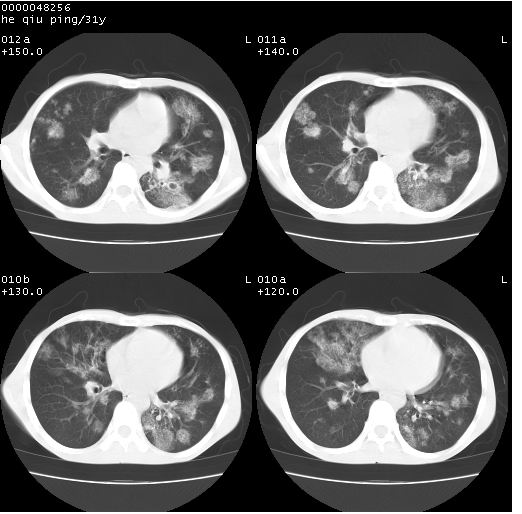

双上肺多发空洞,双飞散在分布大小不一的片状结高密度影节状大片状高密度影。符合结合肉芽肿形成及空洞形成。

双侧弥漫性病变,双上叶尖后段、下叶北段见多个空洞,多见于结核感染。右中叶及双下叶斑片状,结节状影,考虑为肉芽肿形成及支气管播散。但由于患者消瘦体质,抵抗力低下,若继发感染,如金葡菌肺炎也有可能。

考虑为:两肺结核伴多发空洞形成、支气管播散。

结核空洞并播散,玫瑰花簇征。

病灶多形性,有空洞形成。考虑肺结核伴空洞形成,两下肺支气管播散!